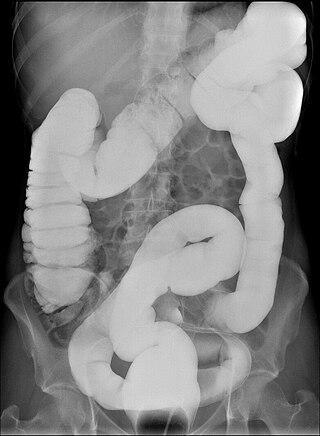

Долихоколон — аномалия развития кишечника, удлинение одного из отделов или всей ободочной кишки. Имеет клиническое значение — может приводить к болям в животе и запорам. Является самой частой аномалией развития толстой кишки.